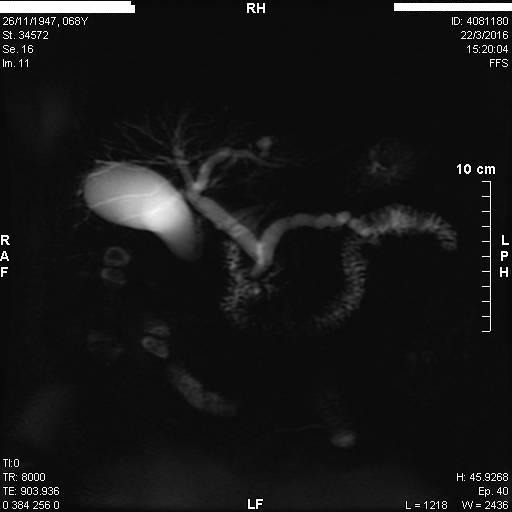

Άνδρας 61 ετών με ανώδυνο αποφρακτικό ίκτερο υποβλήθηκε σε μαγνητική τομογραφία που έδειξε διάταση ενδοηπατικών χοληφόρων με στένωση του κοινού ηπατικού πόρου και της συμβολής του δεξιού και αριστερού ηπατικού πόρου, εικόνα συμβατή με χολαγγειοκαρκίνωμα της πύλης του ήπατος (όγκος Klatskin, Bismuth IV). Επίσης συνυπήρχε θρόμβωση πυλαίας φλέβας, ασκιτικό υγρό και ευμεγέθεις λεμφαδένες πέριξ της κεφαλής του παγκρέατος και στον ηπατοδωδεκαδακτυλικό σύνδεσμο. Το νεόπλασμα κρίθηκε ανεγχείρητο μετά από συζήτηση σε συμβούλιο πολλαπλών ειδικοτήτων και ο ασθενής υποβλήθηκε σε ενδοσκοπική παλίνδρομη χολαγγειο-παγκρεατογραφία (ERCP) για αποσυμφόρηση του ικτέρου. Στην ERCP έγινε λήψη κυττάρων από την περιοχή της στένωσης με βούρτσα κυτταρολογικής, διαστολή της στένωσης με μπαλόνι και επιτυχής τοποθέτηση ακάλυπτου, μεταλλικού stent μήκους 10εκ. Μετά την ERCP, ο ασθενής βελτιώθηκε κλινικά με σημαντική υποχώρηση του ικτέρου.

MRI: απόφραξη κοινού ηπατικού πόρου με διάταση ενδοηπατικών χολαγγείων

ΜRCP: διάταση παγκρεατικού πόρου